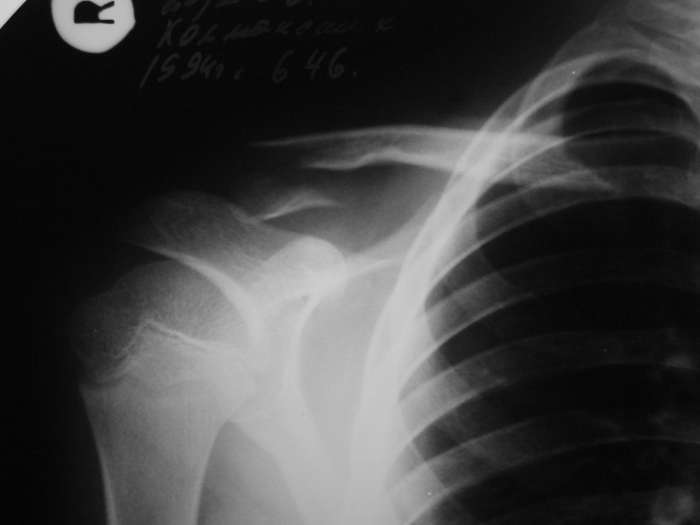

НЗ> 2. Нет ли на снимке перелома хирургической шейки плеча? Сам

Нет.

Александр Николаевич, не покажете в картинках, как соорудить такой пелот?

Александр, простите за настойчивость, на картинке я указал смутившую меня тень ... это вариант зоны роста?

> смутившую меня тень ... это вариант зоны роста?

Это контур зона роста на передней поверхности кости.

Перелома плеча нет, это зона роста с другой стороны кости.

По поводу проксимального плеча, согласен с вами, перелома нет - видна линия ростковой зоны.